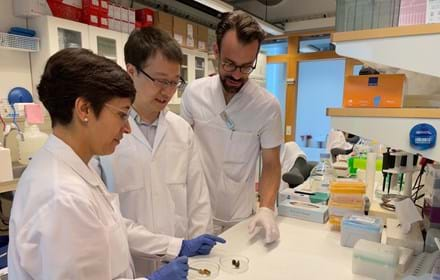

Diabetesforskning för alla!

Ansök om forskningsanslag

Satsning på precisionsmedicin och diabetes